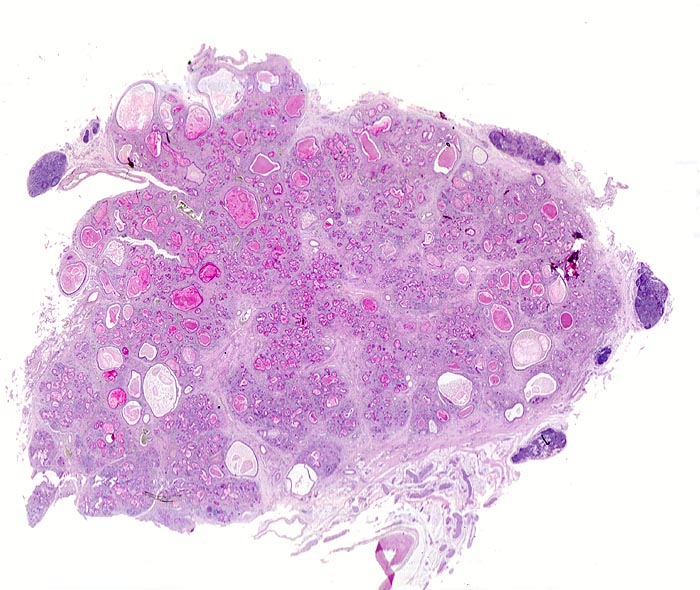

Fast alle exokrinen Drüsen sind betroffen. Pankreasgänge, intestinale Drüsen, intrahepatische Gallengänge und die Glandula submandibularis sind obstruiert durch visköses oder solides eosinophiles Material. Tracheobronchiale und Brunner’sche Drüsen bilden vermehrten Schleim. Schweissdrüsen, kleine Speicheldrüsen und Glandula Parotis sind histologisch normal, sezernieren aber vermehrt Natrium und Chlorid. Veränderungen in der Lunge ( 3689) entwickeln sich als Folge von Luftwegsobstruktion und Infekten (initial vor allem mit Staphylococcus aureus, später meist Pseudomonas aeruginosa).